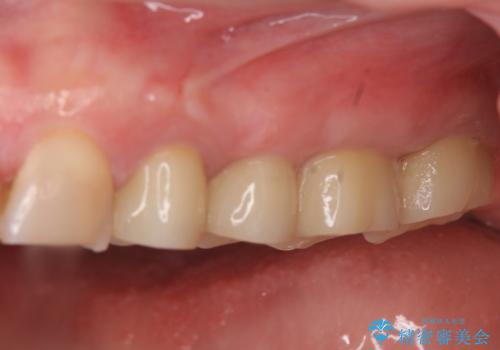

放置した虫歯 根管治療 フルジルコニアクラウン

樹脂やクラウン・銀歯の老朽化がみられるため、丁寧に除去を行い根管治療を行ったのち、歯軋り・厚みの少なさを鑑みフルジルコニアクラウンによる補綴を計画します。

- 38万円(仮歯・ファイバーコア・フルジルコニアクラウン×4)費用は治療当時の料金となります